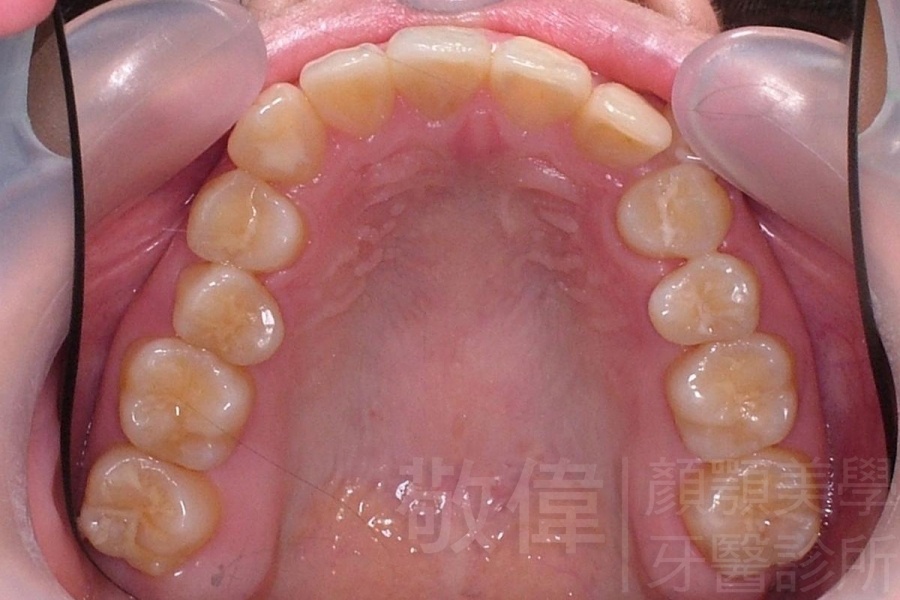

齒顏矯正/上顎暴牙且牙齒極度混亂

矯正前-上   矯正前-下

<個案說明>

上顎暴牙且牙齒極度混亂,經由矯正之後,臉型大幅度改善,牙齒的排列更加的整齊健康。相較於之前眼神充滿精神,自信心展現無遺。